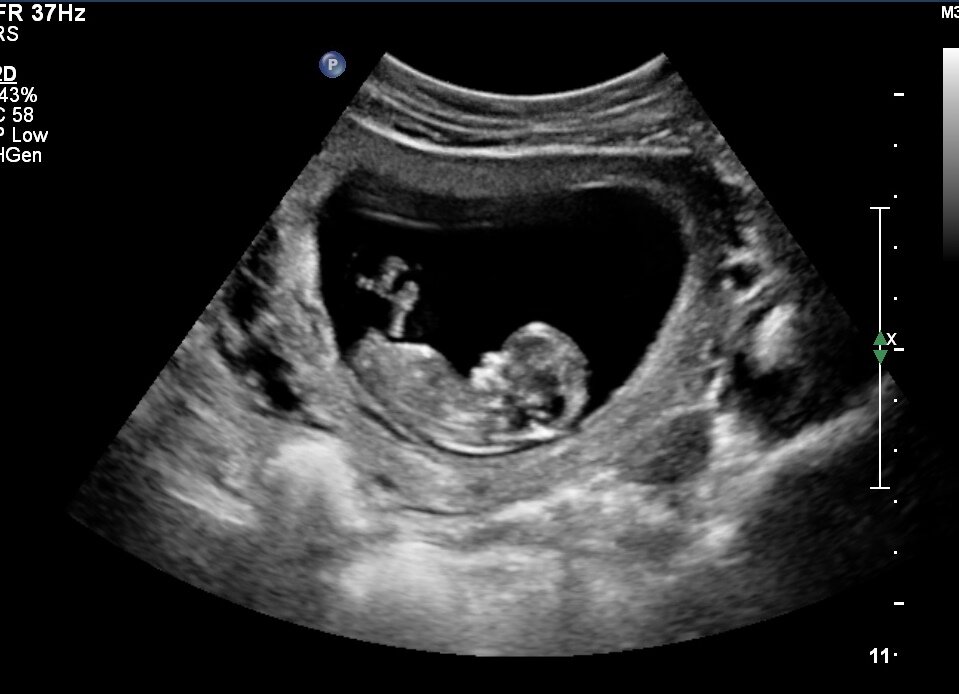

Аборт